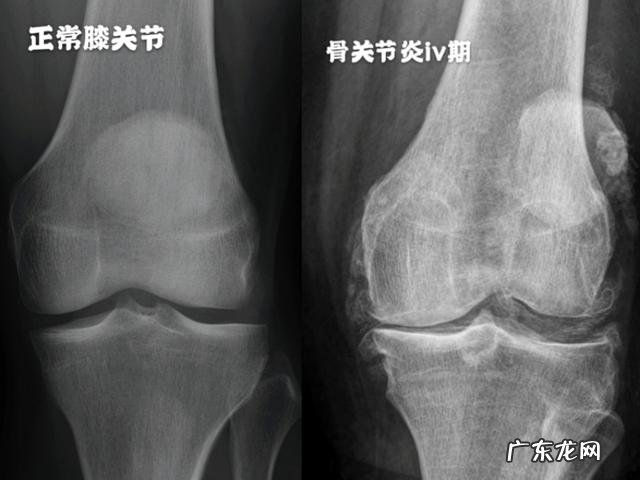

病例三:七十岁老年女性 , 双膝疼痛难忍这位患者是本院一位护士的亲属 , 70岁的老年女性 , 由他人搀扶着步入诊室 , 双膝关节呈现明显的o型腿改变 , 畸形特别明显 , 手里拿着她的x线片子 , 看完片子发现双膝关节间隙已经快消失了 , 尤其是内侧膝关节间隙 , 这说明老人的膝关节内的软骨已经磨损的消失殆尽了 , 而且在关节周边有大量的骨赘形成 , 是典型的骨关节炎iv期表现 , 这样的情况应该会明显的影响老人的关节屈伸功能 。

对于这种骨关节炎已经处于4期表现的患者来讲 , 进行膝关节置换是最好的办法 , 可以彻底帮助老人解决问题 , 但是想要让患者接受这么大的手术往往是非常难的 , 再给老人查体后发现她的关节积液特别多 , 老人关节表现出来的胀痛特别明显 , 已经严重影响老人的屈伸功能 , 所以与家人进行了仔细的探讨以后 , 决定暂时给老人采取保守zhi疗 , 门诊给老人化验了血糖 , 化验了血常规 , 并没有特殊的异常 , 之后给老人进行了关节腔穿刺 , 把积液抽出来 , 给予关节腔内注射了玻璃酸钠 , 老人的症状有了一些缓解 , 虽然对于这位老人来讲进行这种zhi疗 , 可能只是杯水车薪 , 能暂时的缓解老人一段时间的症状 , 甚至可能是一周、两周就要疼痛再次加重 , 但是这也给了老人一定思考的时间 , 与家人探讨的时间 , 决定是否要进行关节置换彻底解决问题 。